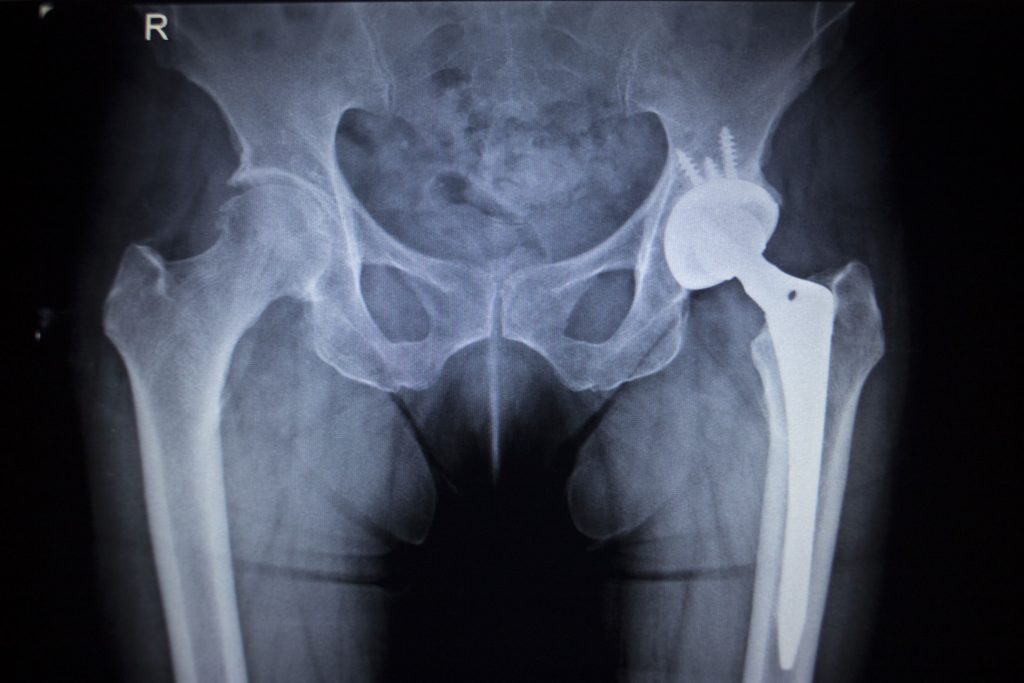

The plaintiffs say the manufacturers’ hip implants suffer from significant design flaws, which include the socket being designed as a metal-on-metal joint. The plaintiffs claim that friction resulting from the metal-on-metal design of the implants can cause the devices to release metal ions into the blood, resulting in painful and sometimes permanent injuries, such as bone erosion and even tissue death.

Though DePuy stopped selling the Pinnacle brand hip implants in 2013, the company’s legal woes appear have no end in sight. DePuy paid out $2.5 billion in 2013 to settle over 7,000 lawsuits relating to another faulty metal-on-metal hip implant, which had been the subject of a recall. Together, Johnson & Johnson and DePuy are facing over 8,000 additional lawsuits relating to defective hip implants.